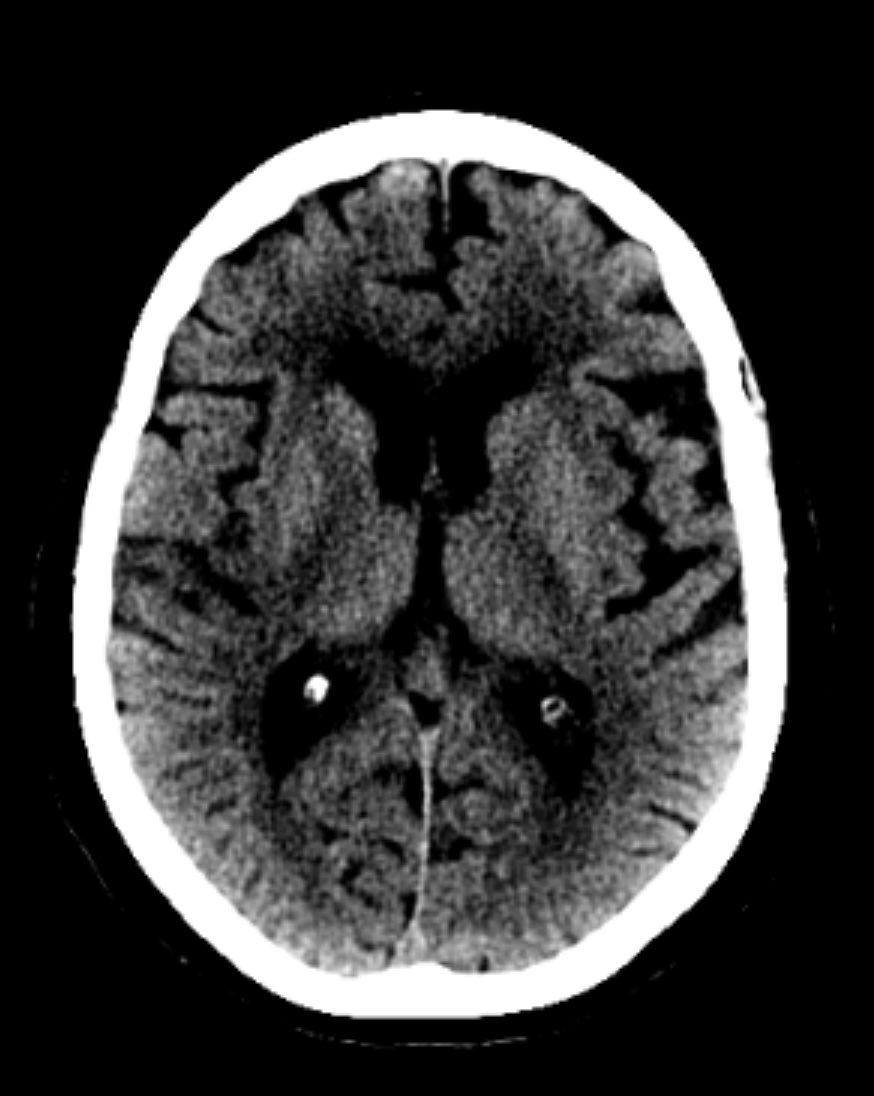

👀A pictorial #MeVO case review🖼️with discussion of state of the art evidence: superbly written by A. Ciacciarelli and G. Busto🤩 #INR #stroke #neurorad ➡️ rdcu.be/e6MIa